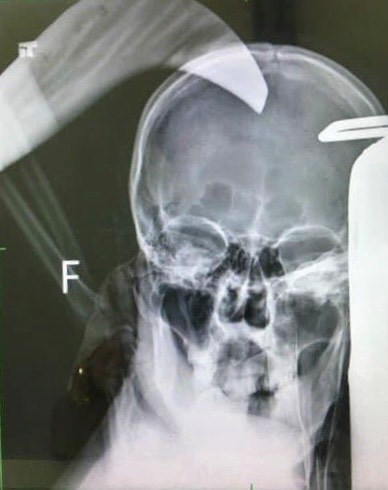

Hình ảnh chụp X-quang phần đầu của nạn nhân.

Ngoài ra, thông tin trên tờ VOV cho biết, nạn nhân sau đó được đưa đến Bệnh viện Đa khoa tỉnh Quảng Ninh trong tình trạng đa chấn thương vùng đầu, hung khí ngập vào não sâu khoảng 5cm, gây rách vỏ não, dập não, chảy máu não.

Các bác sỹ đã tiến hành phẫu thuật bóc tách hung khí trên đầu nạn nhân, lấy não dập, máu tụ, dị vật và mảnh xương vỡ găm vào não. Sau 2h đồng hồ, nạn nhân đã qua cơn nguy kịch và hiện đang được thở máy.